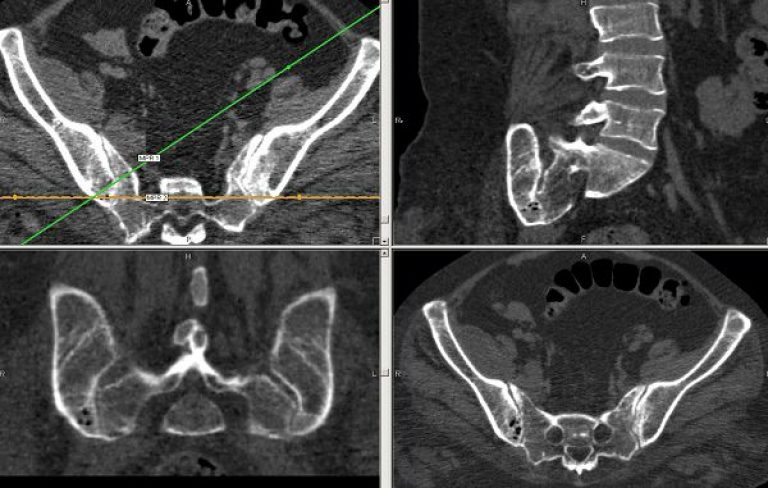

МРТ крестцово-подвздошных сочленений - это информативный и эффективный метод исследования для оценки состояния крестцово-подвздошных (сакроилеальных) суставов. Диагностика позволяет визуализировать, кроме костной основы, мягкие ткани указанной области (хрящевые структуры, связочный аппарат, мышечный корсет). Магнитно-резонансная томография тазовой области применяется для диагностики заболеваний дегенеративного, воспалительного характера, онкологической патологии.

Кроме того, благодаря МРТ крестцово-подвздошных сочленений и костей таза доктор может на ранней стадии обнаружить сакроилеит, болезнь Бехтерева, некоторые артриты, что обеспечит более эффективное и успешное лечение.

Что показывает МРТ крестцово-подвздошных сочленений? Благодаря диагностике лечащий врач получает возможность обнаружить у человека:

- травматическое повреждение крестцово-подвздошных суставов;

- анатомические нарушения в строении сочленения;

- деформацию сочленений, изменение их структуры и формы;

- подтвердить наличие остеофитов, экзостозов, участков опухолевого роста, метастазов.

МРТ отлично визуализирует онкологическую патологию: вплоть до структуры, размеров, формы опухоли или метастазов.